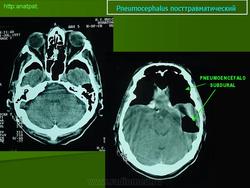

Por tanto Neumocéfalo o neumoencéfalo son términos utilizados por los Radiólogos para describir la existencia de aire acumulado en cualquiera de los espacios de la cavidad craneal (Figura 1).

A) NEUMOCÉFALO POSTRAUMÁTICO: Es una complicación muy grave de un traumatismo craneoencefálico y se produce por fractura de la pared de los senos paranasales o de la base del cráneo. Cuando una persona sufre un accidente muy violento, como sucede en los de tráfico, se producen múltiples fracturas de cráneo. Si alguna rompe la pared de los senos paranasales y una esquirla ósea desgarra la duramadre, el aire penetra al interior del cráneo y se acumula en cualquiera de los espacios intracraneales, aunque fundamentalmenteen el subaracnoideo. En el topograma preliminar de una TC se aprecia una imagen hipodensa que representa el gas depositado en el espacio subaracnoideo frontal (flechas) porque al realizar la exploración en decúbito supino el aire asciende hacia las partes más elevadas de la cavidad craneal. (Figura 1).

FIGURA 1) Neumocéfalo postraumático. El aire, que ha penetrado en el espacio subaracnoideo de las cisternas basales como consecuencia de la fractura del techo del seno esfenoidal y de la duramadre, asciende por gravedad al espacio subaracnoideo frontal, donde forma un nivel (flechas)